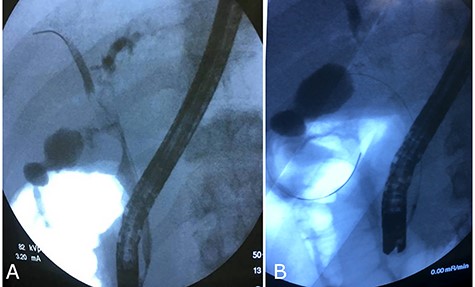

After fourth month, laboratory tests were normal so ERCP with removal of plastic biliary stent was performed and cholangiography post-removal showed a free and restored biliary tree (Fig. 4).